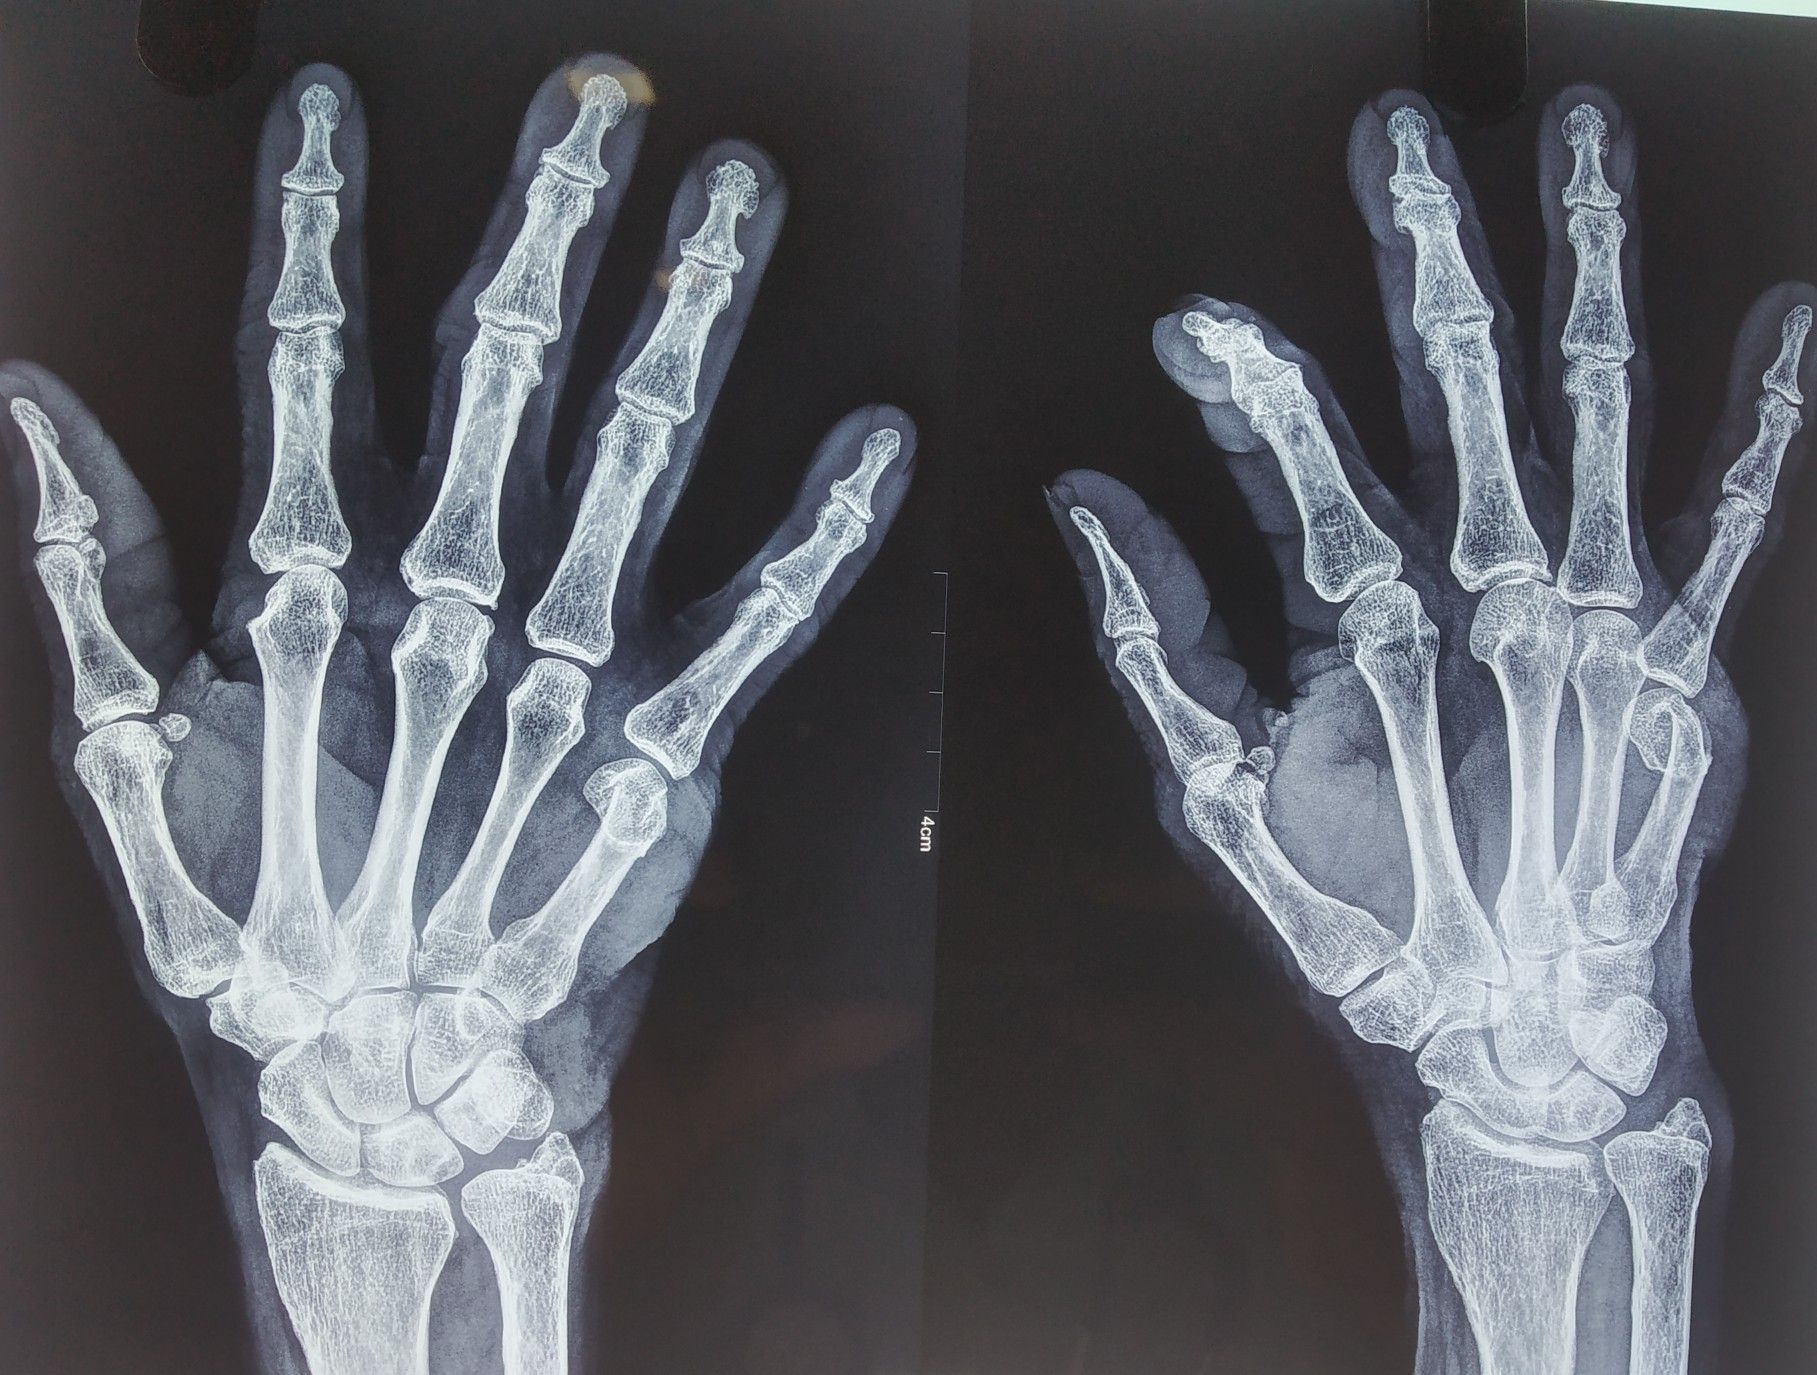

find the fracture

Fracture

Hand

Metacarpal

The first metacarpal

no

boxer's fracture